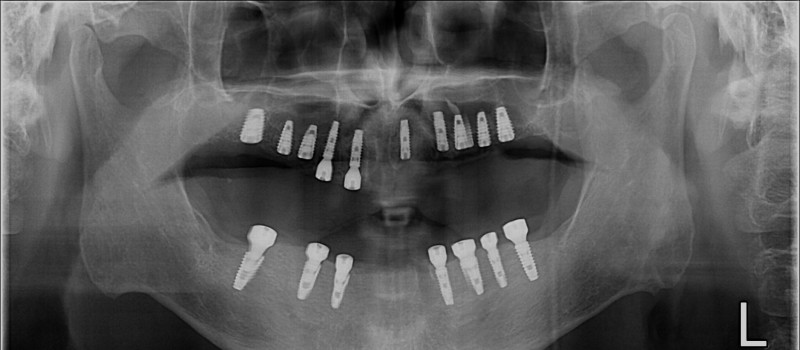

무치악 임플란트 회복

무치악 임플란트 회복 Full Mouth Rehabilitation

중간과정 ▼